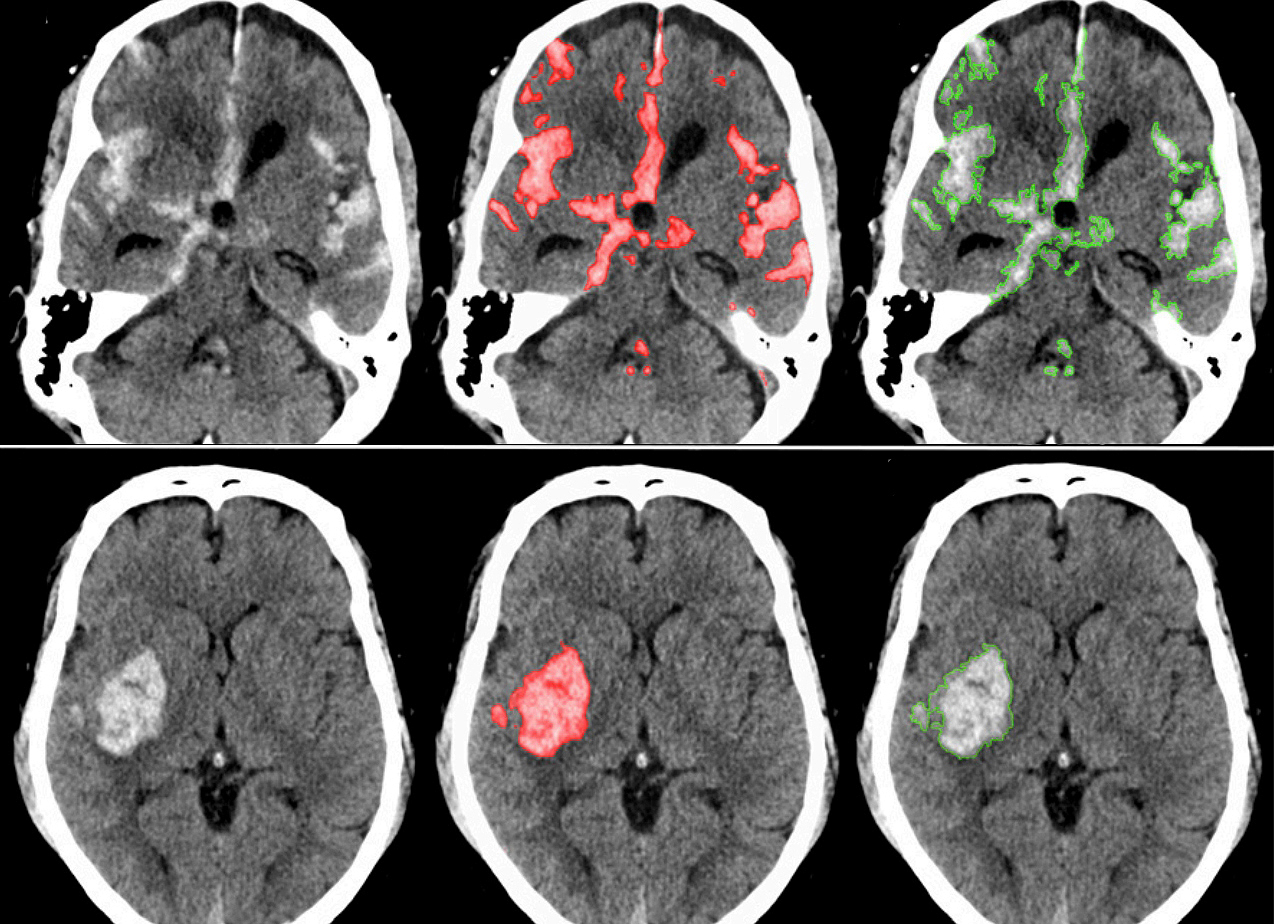

뇌출혈의 발생을 시각화한 이미지

뇌출혈은 뇌 속 혈관이 터져서 피가 나는 질환을 말합니다. 뇌졸중 환자 10명 중 1명 정도가 뇌출혈 진단을 받는다고 합니다. 뇌출혈은 뇌경색과 다르게 특별한 전조 증상이 거의 없다는 것이 특징입니다.

갑자기 발생하며, 그 즉시 심각한 후유증을 남길 수 있어 무엇보다 미리 대비하고 빠르게 대처하는 것이 중요합니다. 뇌출혈은 뇌에 큰 손상을 줄 수 있기 때문에 이 질환에 대해 잘 알아두는 것이 좋습니다.

뇌출혈은 뇌혈관이 파열되어 뇌 안에 출혈이 발생하는 질환입니다. 갑작스럽게 발생하며, 예방과 조기 대응이 매우 중요합니다.